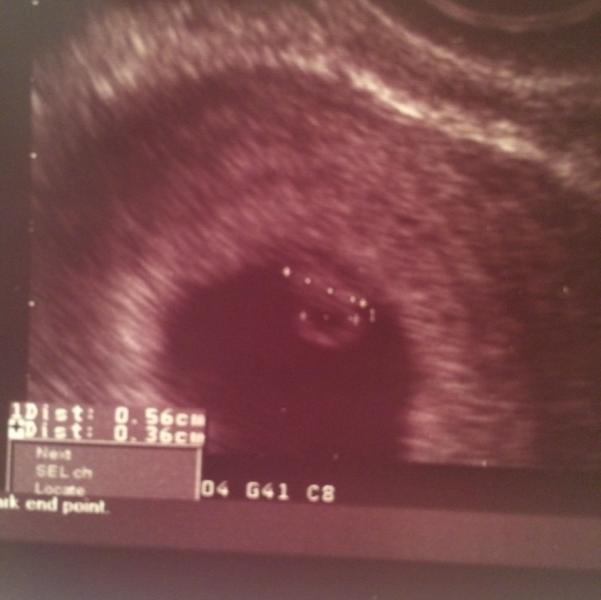

Шла сегодня на УЗИ с опаской.

Мутить меня перестало дня три назад и ничего не болело, грудь тоже не проявляла признаков. А лента моя последнее время все больше с плохими новостями - и так девочек жаль 😞 тем более сама это проходила и так за кроху страшно стало. 😬

Но слава Богу, мы в порядке, сердечко бьется, 6нед1день 5,6 мм козявочка. Оформила контракт, встала на учёт, сдала поллитра крови 😇 вот вам наши фотки 🦁